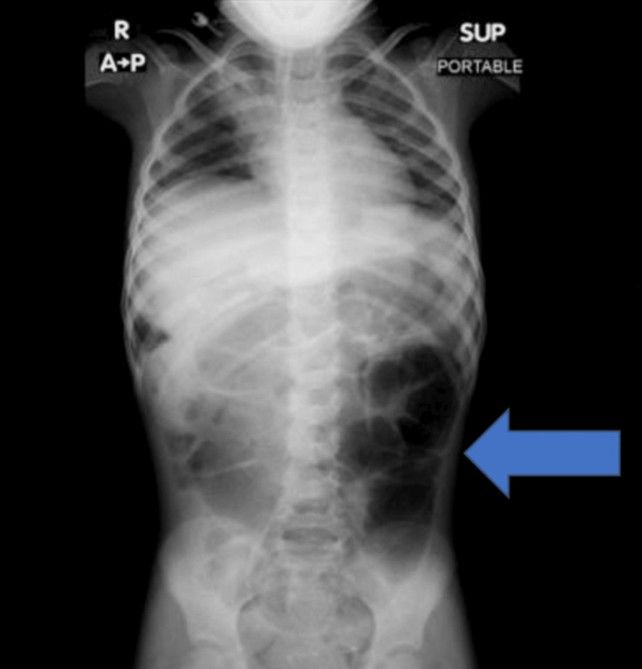

[서울=뉴시스]윤서진 인턴 기자 = 복통을 호소하던 6세 여아의 위장 안에서 예상치 못한 이물질이 발견된 사례가 학술지에 보고됐다.

20일 의학 저널 '큐레우스(Cureus)' 실린 보고에 따르면, 사우디아라비아에 거주하는 6세 여자아이는 수주간 이어진 복통과 소화 장애 증상으로 병원을 찾았다. 정밀 검사를 진행한 결과, 의료진은 위 내부에 비정상적으로 큰 이물질이 자리 잡 것을 확인했다.

의료진은 보고서를 통해 "소아 환자에게 반복적인 복통이나 구토, 식욕 저하 증상이 장기간 지속될 경우 위장관 내 이물질 가능성을 염두에 둬야 한다"며 "영상 검사를 통한 조기 진단과 신속한 치료가 중요하다"고 강조했다.

라푼젤 증후군은 머리카락을 반복적으로 뽑는 행동과 이를 삼키는 습관이 함께 나타나면서, 섭취된 모발이 위장 안에 쌓여 덩어리를 이루는 매우 드문 질환이다.

이 병명은 독일 그림 형제가 소개한 동화 '라푼젤'에서 따왔다. 동화 속 주인공이 높은 탑에서 길게 늘어뜨린 머리카락으로 외부와 이어지는 장면처럼, 실제 질환에서도 머리카락으로 형성된 이물질이 위에서 시작해 실타래처럼 장까지 길게 이어지는 양상을 보이기 때문이다.